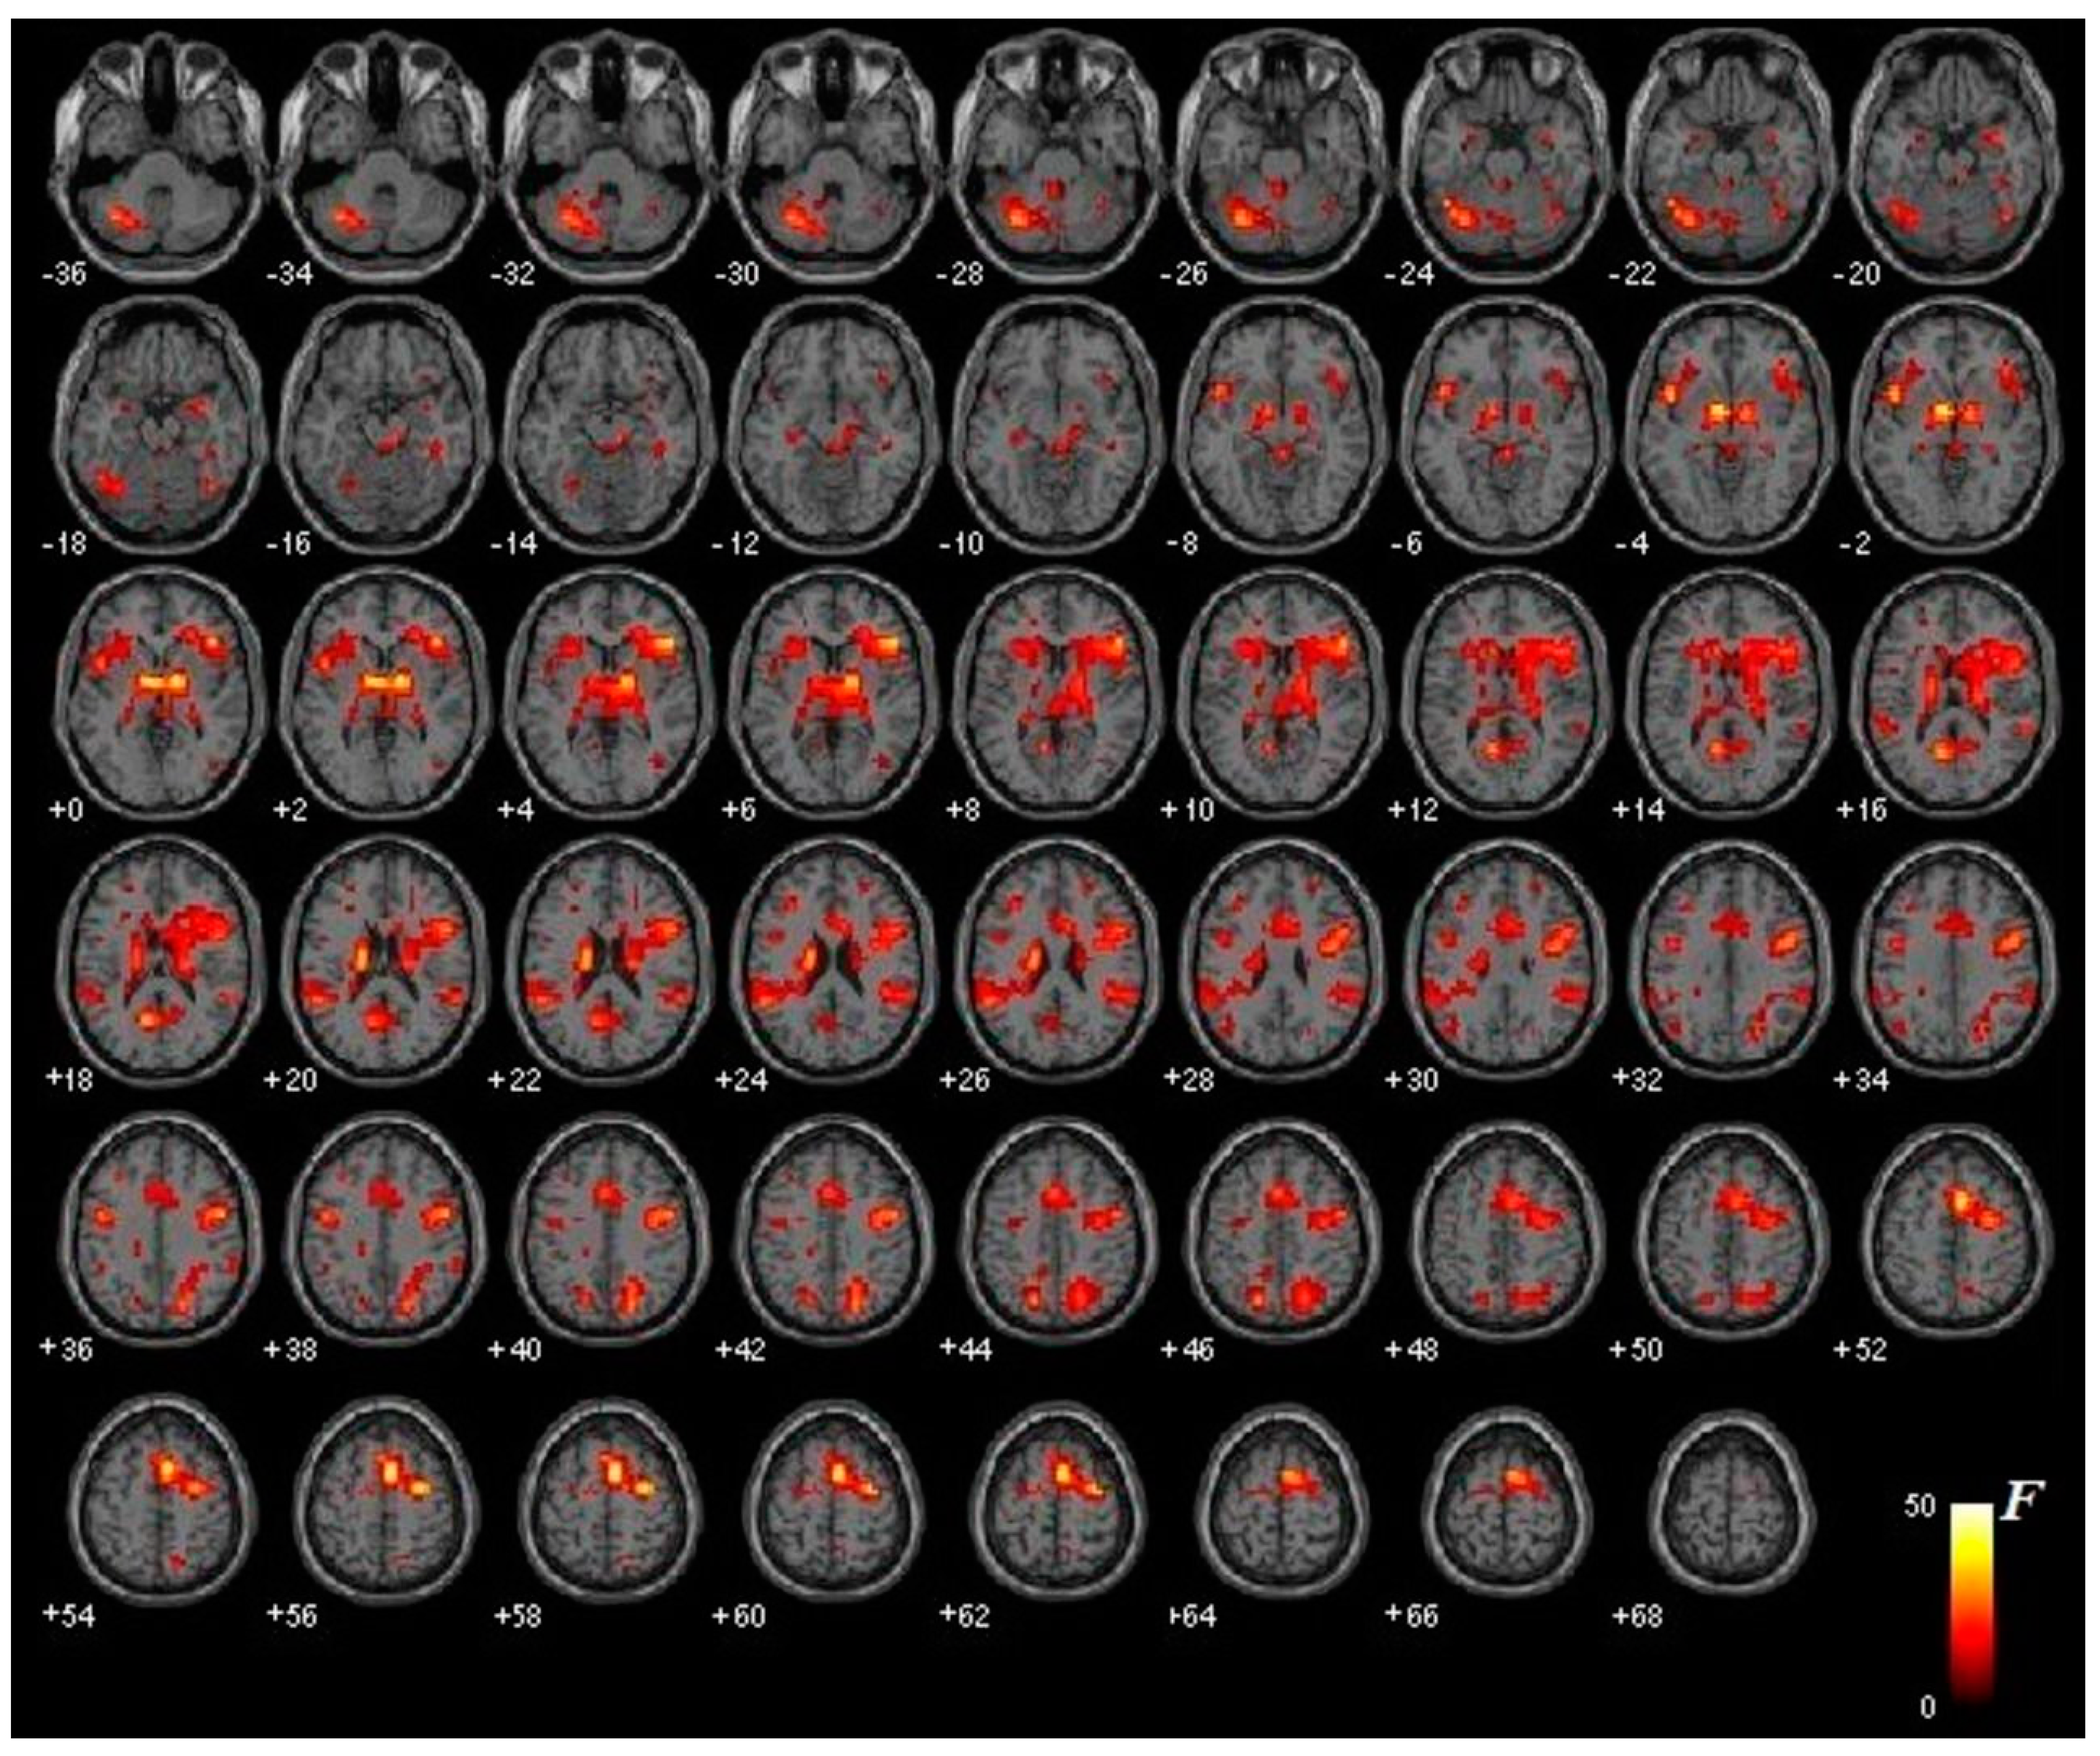

3.2. Functional Brain Activation

3.2.1. Thalamus

3.2.2. Amygdala

3.2.3. Occipital Cortex

3.2.4. Frontal and Prefrontal Cortex

3.2.5. Other Brain Structures Involved in Emotional Regulation and Specific Phobias